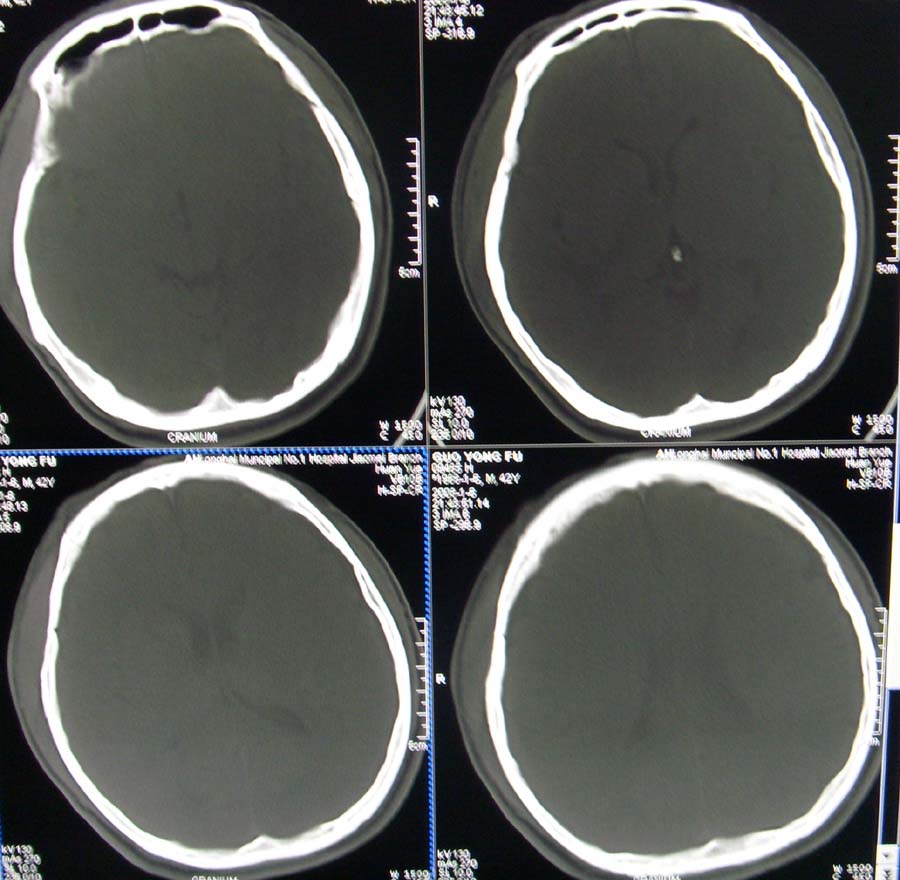

男,45,外伤体检,请问骨窗最后一层板障内低密度影是正常吗

蛛网膜颗粒压迹.

蛛网膜颗粒压迹。

蛛网膜颗粒压迹,为正常表现。